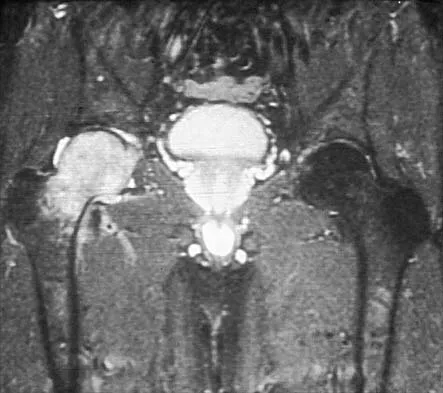

Question 70

A 28-year-old woman who is an avid runner reports pain about the left hip with activities. Nonsurgical management has failed to provide relief. An MRI arthrogram is shown in Figure 47. What is the most likely diagnosis?

Explanation